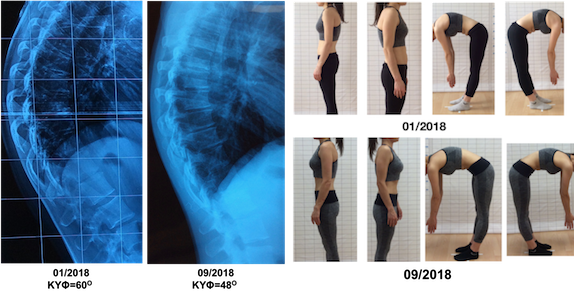

Η αντιμετώπιση της κύφωσης τύπου Scheuermann είναι ως επί το πλείστον συντηρητική, με την χρήση κηδεμόνα και ειδικών ασκήσεων για την κύφωση. Σε αντίθεση με την σκολίωση, όπυ η φυσική εξέλιξη τηα πάθησης έχει μελετηθεί διεξοδικά, η φυσική εξέλιξη της κύφωσης τύπου Scheuermann είναι απροσδιόριστη και δεν υπάρχουν ερευνητικά δεδομένα που να επιτρέπουν την πρόγνωση της εξέλιξης της. Εντούτοις, στους κύκλους των διεθνών επιστημονικών κοινοτήτων ο θεραπευτικός ρόλος του κηδεμόνα είναι αναμφισβήτητος. Η Scoliosis Research Society (SRS) στις οδηγίες της για την θεραπεία της κύφωσης τύπου Scheuermann αναφέρει ρητά πως ο κηδεμόνας πρέπει να εφαρμόζεται μόνο σε παιδιά με γωνία Cobb 55 – 80 μοίρες και όταν το παιδί δεν έχει ολοκληρώσει ακόμα την οστική του ανάπτυξη, δηλαδή σε στάδιο ανάπτυξης Risser 0-3. Σε κάποιες περιπτώσεις που έχει γίνει έγκαιρη διάγνωση και η γωνία της κύφωσης δεν έχει μεγαλώσει αρκετά και δεν υπάρχει σημαντική δυσκαμψία, ένα πρόγραμμα Ειδικών Ασκήσεων για την Κύφωση ίσως να είναι αρκετό να μην χρειαστεί η εφαρμογή κηδεμόνα. Το ωράριο εφαρμογής του κηδεμόνα μπορεί να ποικίλλει από 16 έως 22 ώρες την ημέρα. Ο μέσος χρόνος εφαρμογής του κηδεμόνα είναι περίπου 2 χρόνια, ενώ πρέπει να αφαιρείται μειώνοντας σταδιακά το ωράριο, κατά το στάδιο του απογαλακτισμού από τον κηδεμόνα (brace weaning phase).

Ο κηδεμόνας αποσκοπεί στην διόρθωση της σφηνοειδούς παραμόρφωσης των σπονδύλων και στο άνοιγμα των μεσοσπονδυλίων διαστημάτων, όσο το παιδί είναι ακόμα στην ανάπτυξη. Σε αντίθεση με την Εφηβική Ιδιοπαθή Σκολίωση, που η διατήρηση του διορθωτικού αποτελέσματος του κηδεμόνα παραμένει σε αμφισβήτηση, οι έρευνες έχουν δείξει πως το θεραπευτικό αποτέλεσμα του κηδεμόνα στην κύφωση τύπου Scheuermann φαίνεται να διατηρείται, παρότι ενδέχεται να προκληθεί μια ελαφριά επιδείνωση το πρώτο διάστημα αφαίρεσης του κηδεμόνα. Σύμφωνα με τις διεθνείς επιστημονικές κοινότητες SRS και SOSORT, η εφαρμογή ενός κηδεμόνα πάντα πρέπει να συνοδεύεται από ειδικές ασκήσεις για την κύφωση. Μάλιστα οι επιστήμονες της SOSORT προτείνουν οι ειδικές ασκήσεις για την κύφωση να προηγούνται της αρχικής εφαρμογής του κηδεμόνα, με σκοπό να βελτιώσουν την ελαστικότητα της σπονδυλικής στήλης και να συνδράμουν στο διορθωτικό αποτέλεσμα του κηδεμόνα. Σε έντονη δυσκαμψία της σπονδυλικής στήλης η εφαρμογή κηδεμόνα χωρίς Ειδικές Ασκήσεις για την Κύφωση δεν θα έχει κανένα αποτέλεσμα, καθώς δεν θα επιτυγχάνεται κάποια διόρθωση από την πίεση του κηδεμόνα.

Σημαντικός προγνωστικός παράγοντας για το θεραπευτικό αποτέλεσμα είναι η ικανοποιητική διόρθωση την ώρα που το παιδί φοράει τον κηδεμόνα (in-brace correction), η οποία θα πρέπει να είναι minimum 15 -20 μοίρες . Επίσης, αυτονόητο είναι πως καθοριστική σημασία έχει και η συνέπεια με την οποία το παιδί φοράει τον κηδεμόνα και εκτελεί το πρόγραμμα των ειδικών ασκήσεων.